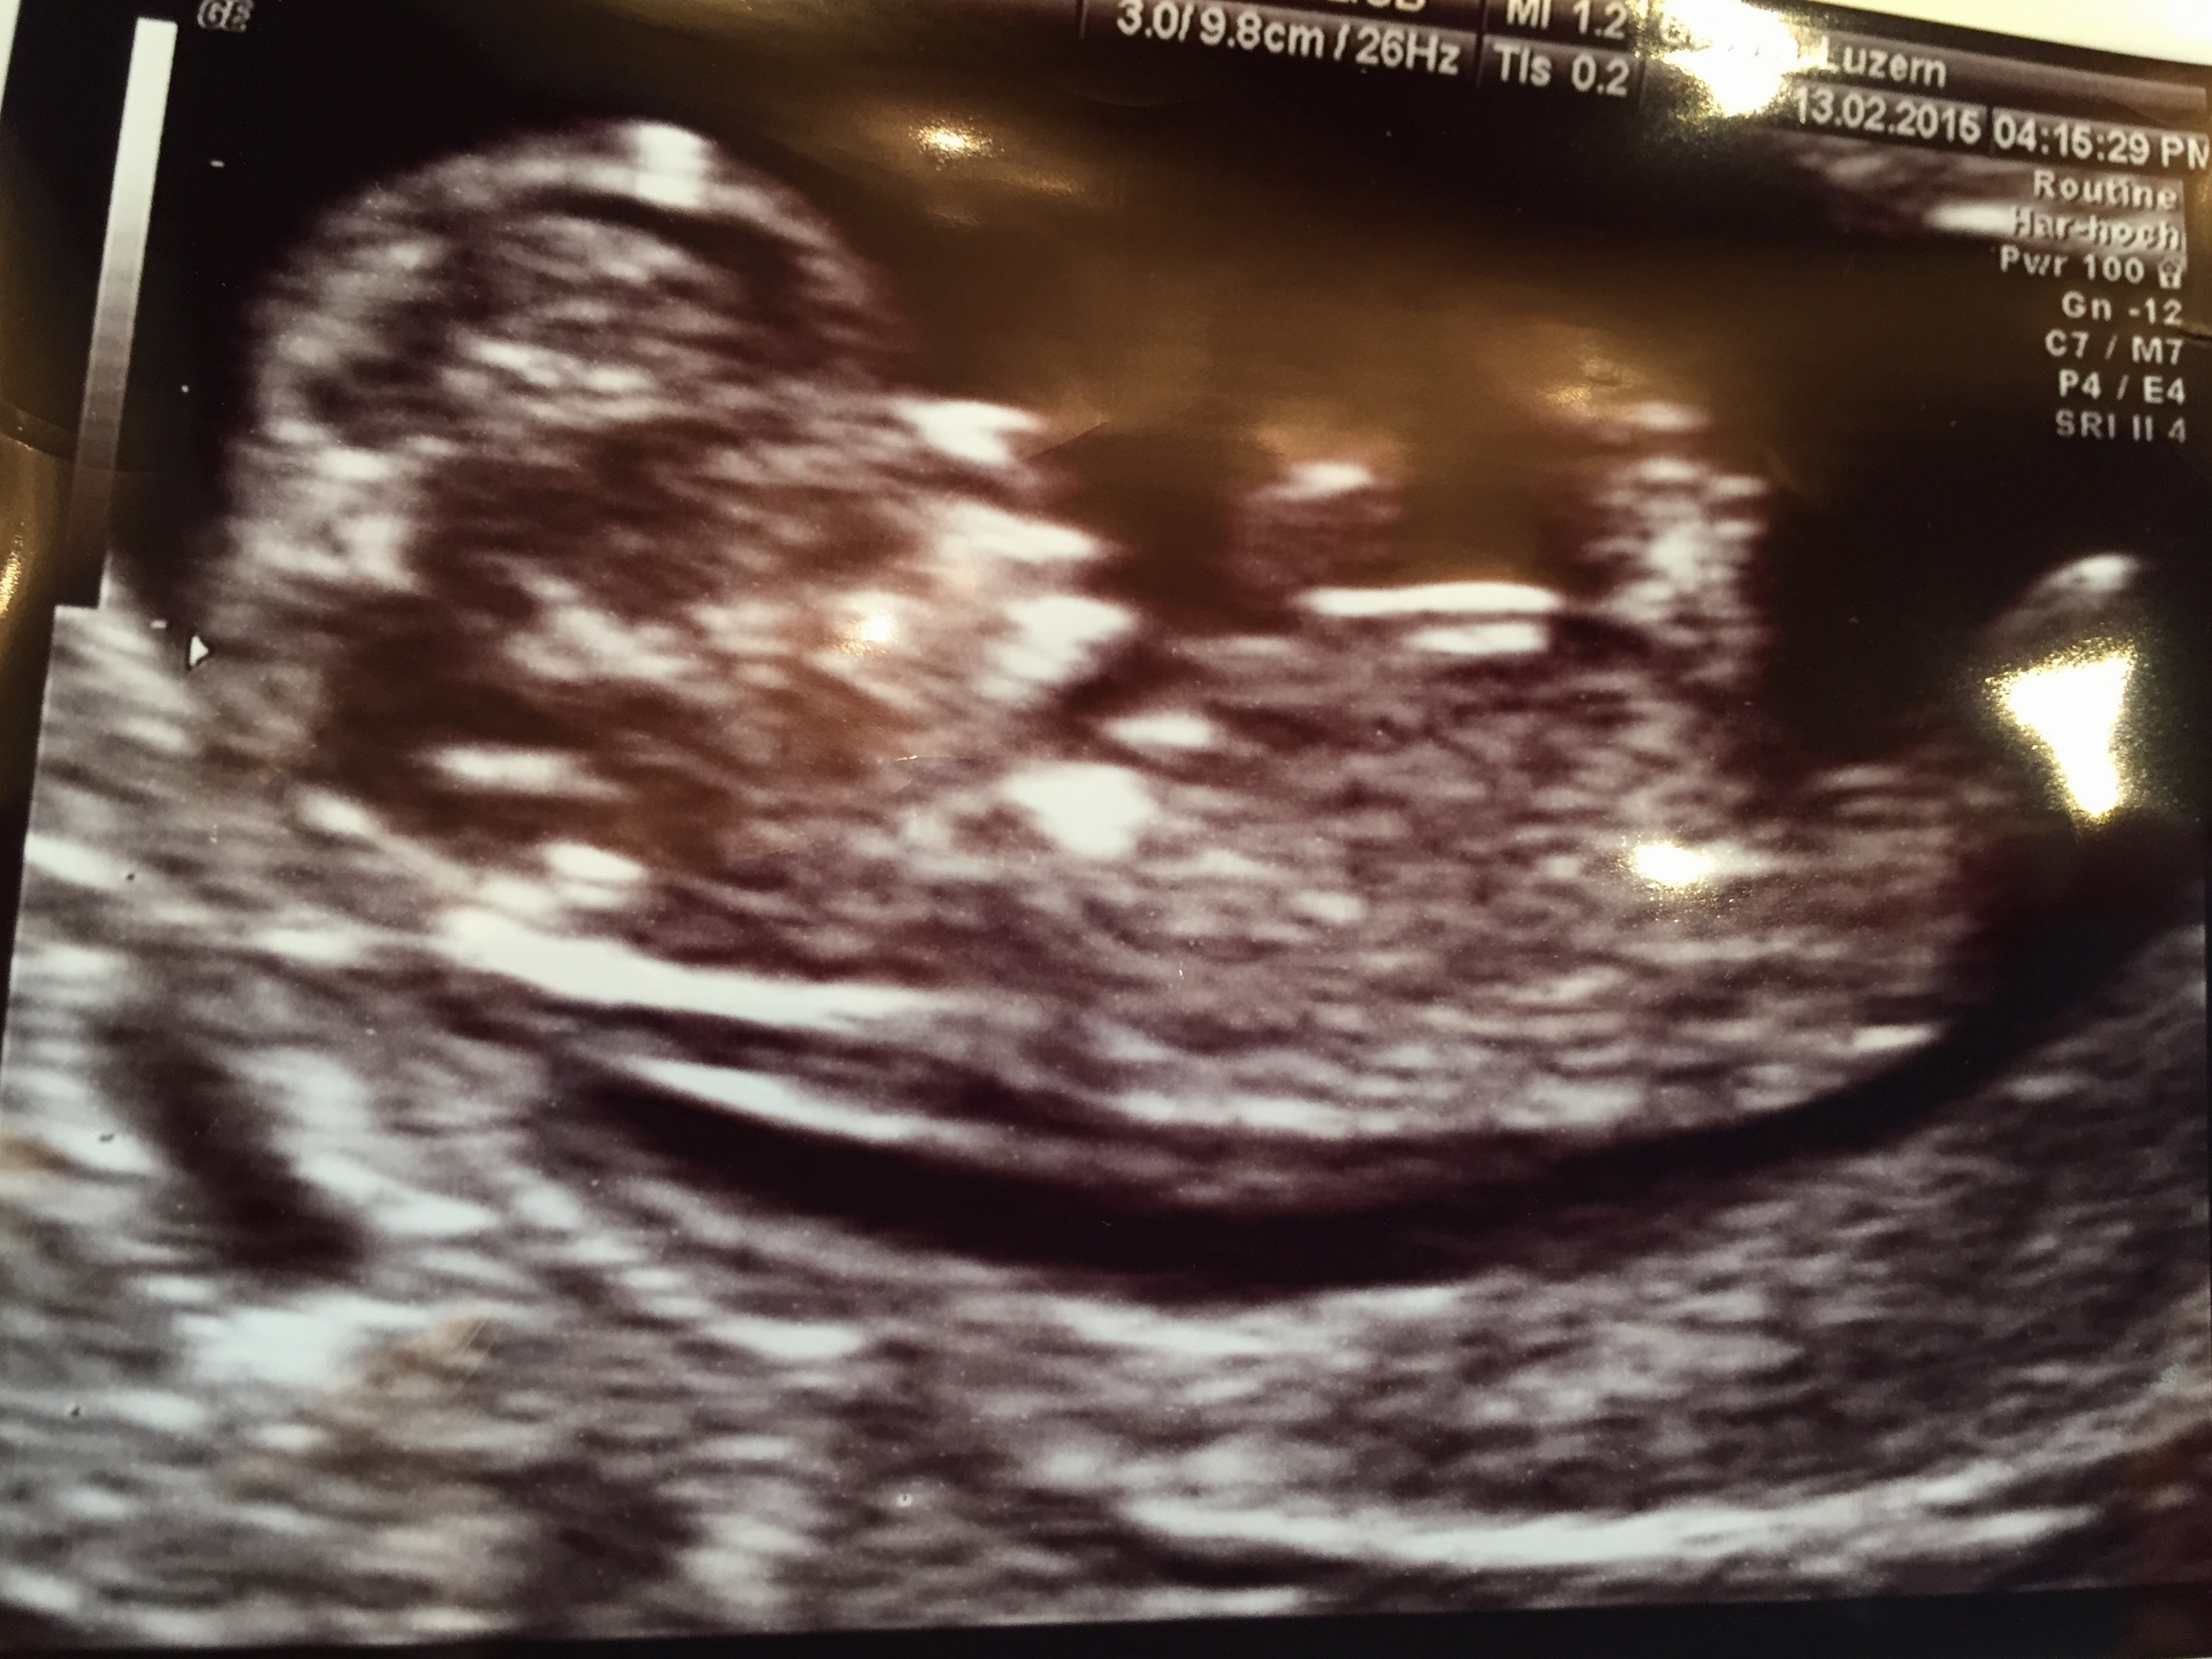

19. Februar 20156. Juli 2015 Zwischenstopp in zwei Akten. Nachtrag. 0 Comments Ein kurzer Abstecher nach Zürich war es. Erster Akt: Wunderbare Neuigkeiten. Nein, ist nicht meins. Also schon. Aber ’nur‘ als Patin. Wie ich mich freu! Zweiter Akt: Leider weniger gute News… Ich bin bei Dir. Du packst das! Teilen mit: Auf X teilen (Wird in neuem Fenster geöffnet) X Auf Facebook teilen (Wird in neuem Fenster geöffnet) Facebook Gefällt mir Wird geladen … Ähnliche Beiträge Autorin